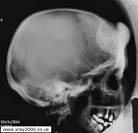

1 2 3

Рис.11. 1 - туберкулезный остит; 2 – артритическая| фаза; 3 - постартритическая| фаза (фиброзный анкилоз).